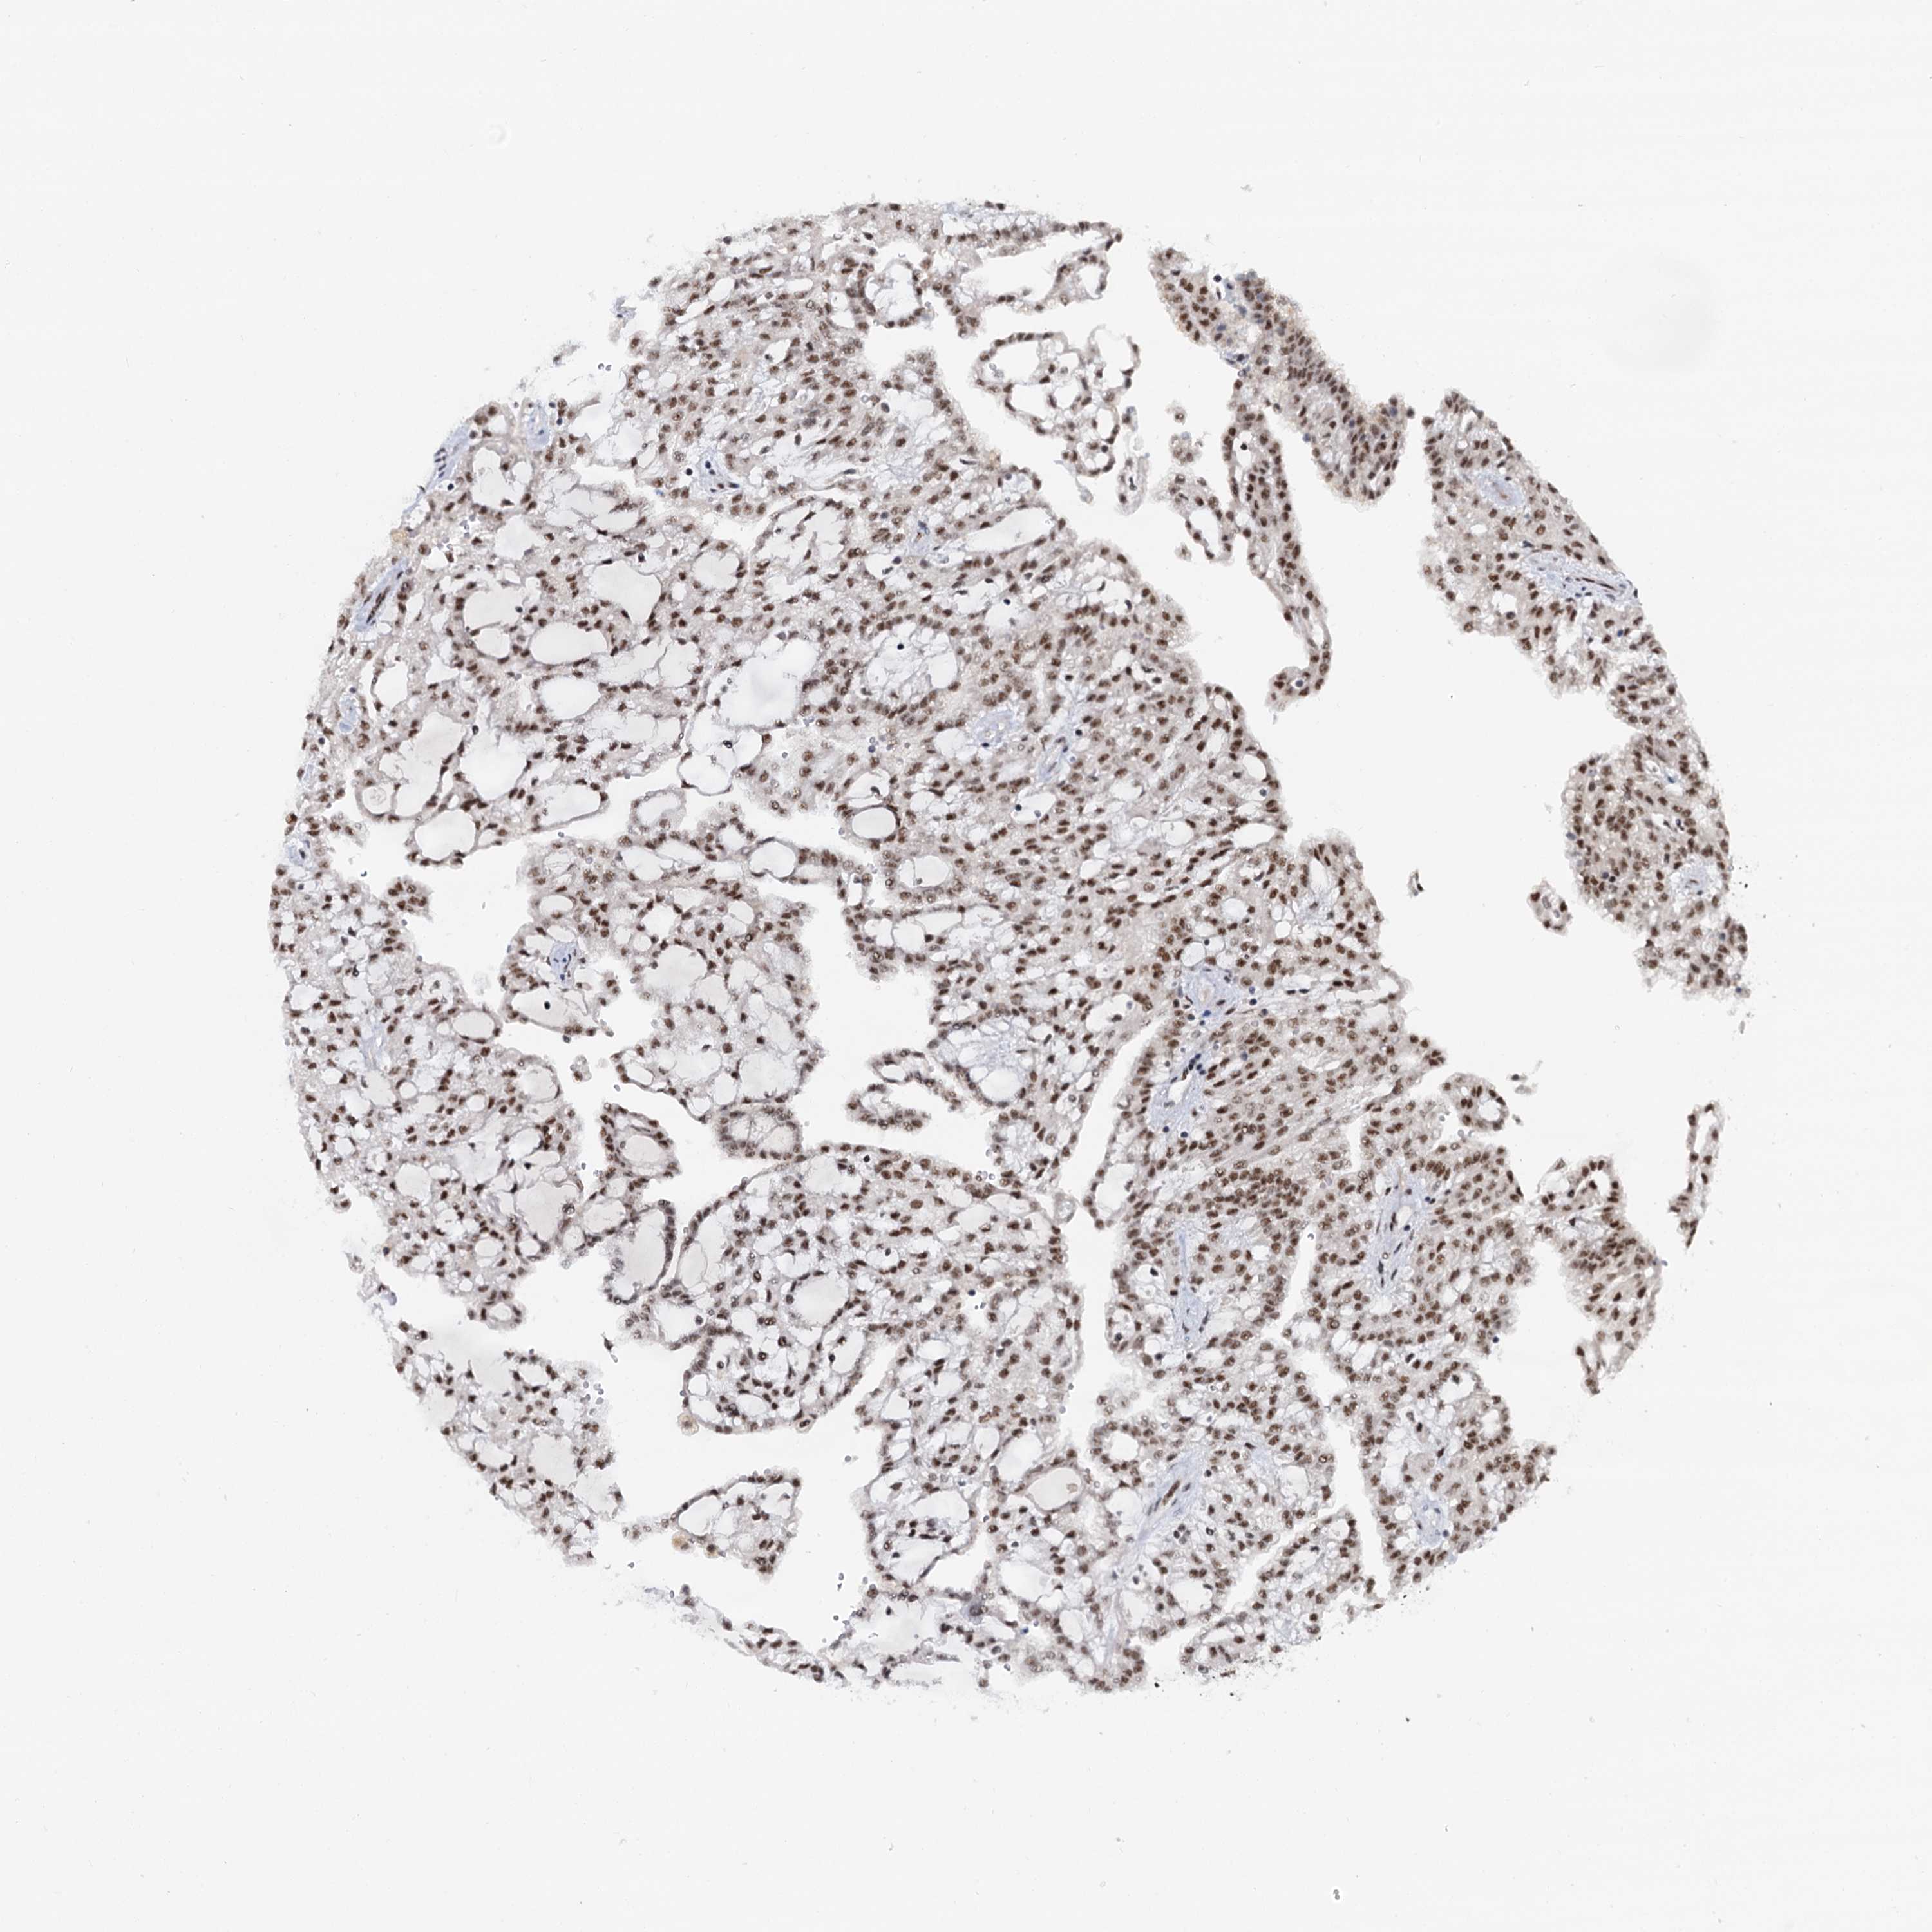

Renal cancer

Kidney renal clear cell carcinoma

WBP4 is potential prognostic, high expression is favorable in Kidney Renal Clear Cell Carcinoma (TCGA)

Average pTPM 10.3

Number of samples 521